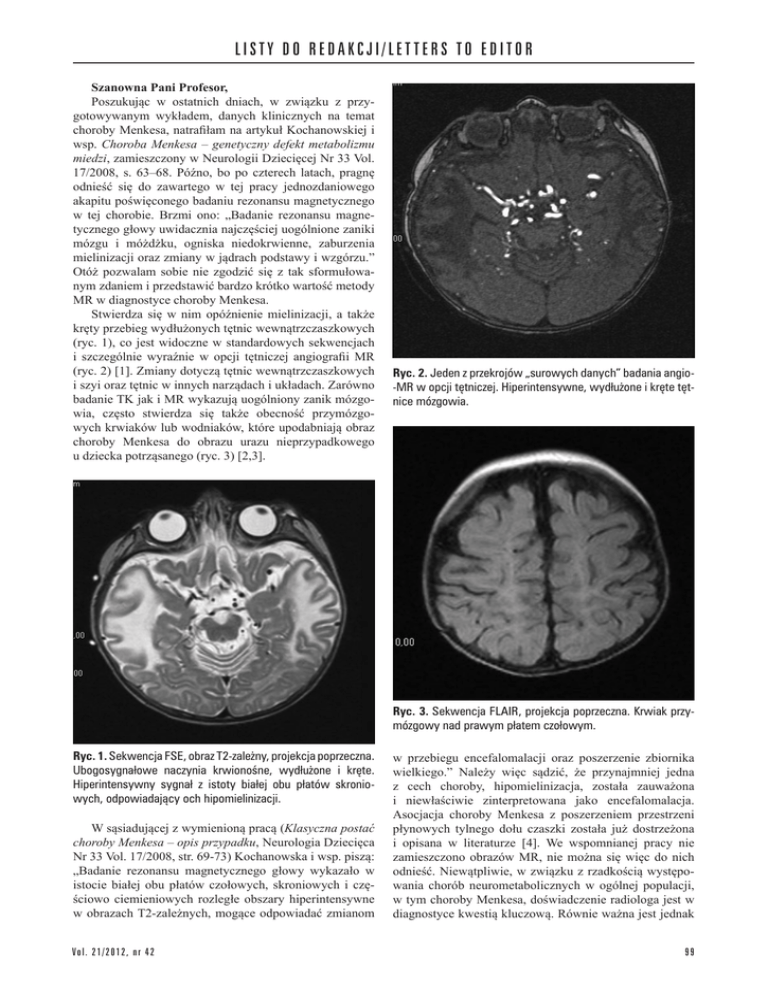

Ryc. 1. Sekwencja FSE, obraz T2-zależny, projekcja poprzeczna.

Ubogosygnałowe naczynia krwionośne, wydłużone i kręte.

Hiperintensywny sygnał z istoty białej obu płatów skroniowych, odpowiadający och hipomielinizacji.

Stwierdza się w nim opóźnienie mielinizacji, a także

kręty przebieg wydłużonych tętnic wewnątrzczaszkowych

(ryc. 1), co jest widoczne w standardowych sekwencjach

i szczególnie wyraźnie w opcji tętniczej angiografii MR